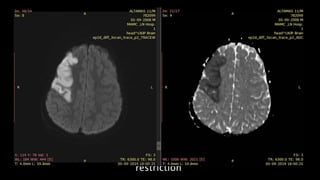

• #50 Here is an example of abnormal linear hypointensity noted in left MCA in the axial SWI image consistent with thrombus. This is called artery susceptibility sign which is considered as MRI correlate of hyperdense MCA seen on NCCT

• #51 Here is another example of 47y old male. FLAIR axial images show shows patchy hyperintensity in left caudate nucleus , lateral putamen and parietal cortex. T2* GRE shows several linear hypointensities in the affected MCA branches, consistent with haemoglobin deoxygenation caused by slow stagnating arterial blood flow.

• #52 DWI of the same patient shows multiple patchy foci of diffusion restriction consistent with ACUTE CEREBRAL INFARCTION. AXIAL 2D MRA shows no flow in the left MCA